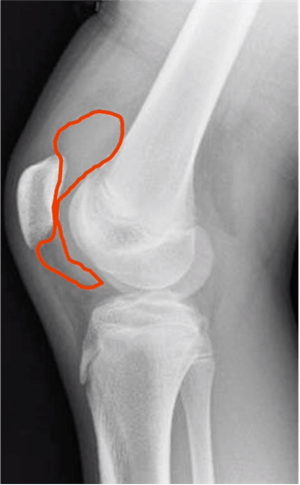

In most cases, especially if the patient heard a “pop” and has acute low back pain, a standing anterior-posterior (AP) and lateral X-ray of the lower lumbar spine is recommended.

X-rays may not show early signs of spondylolysis. Rather than automatically ordering advanced imaging, a pediatric sports or spine referral may be the best next step because MRIs may also be inconclusive.